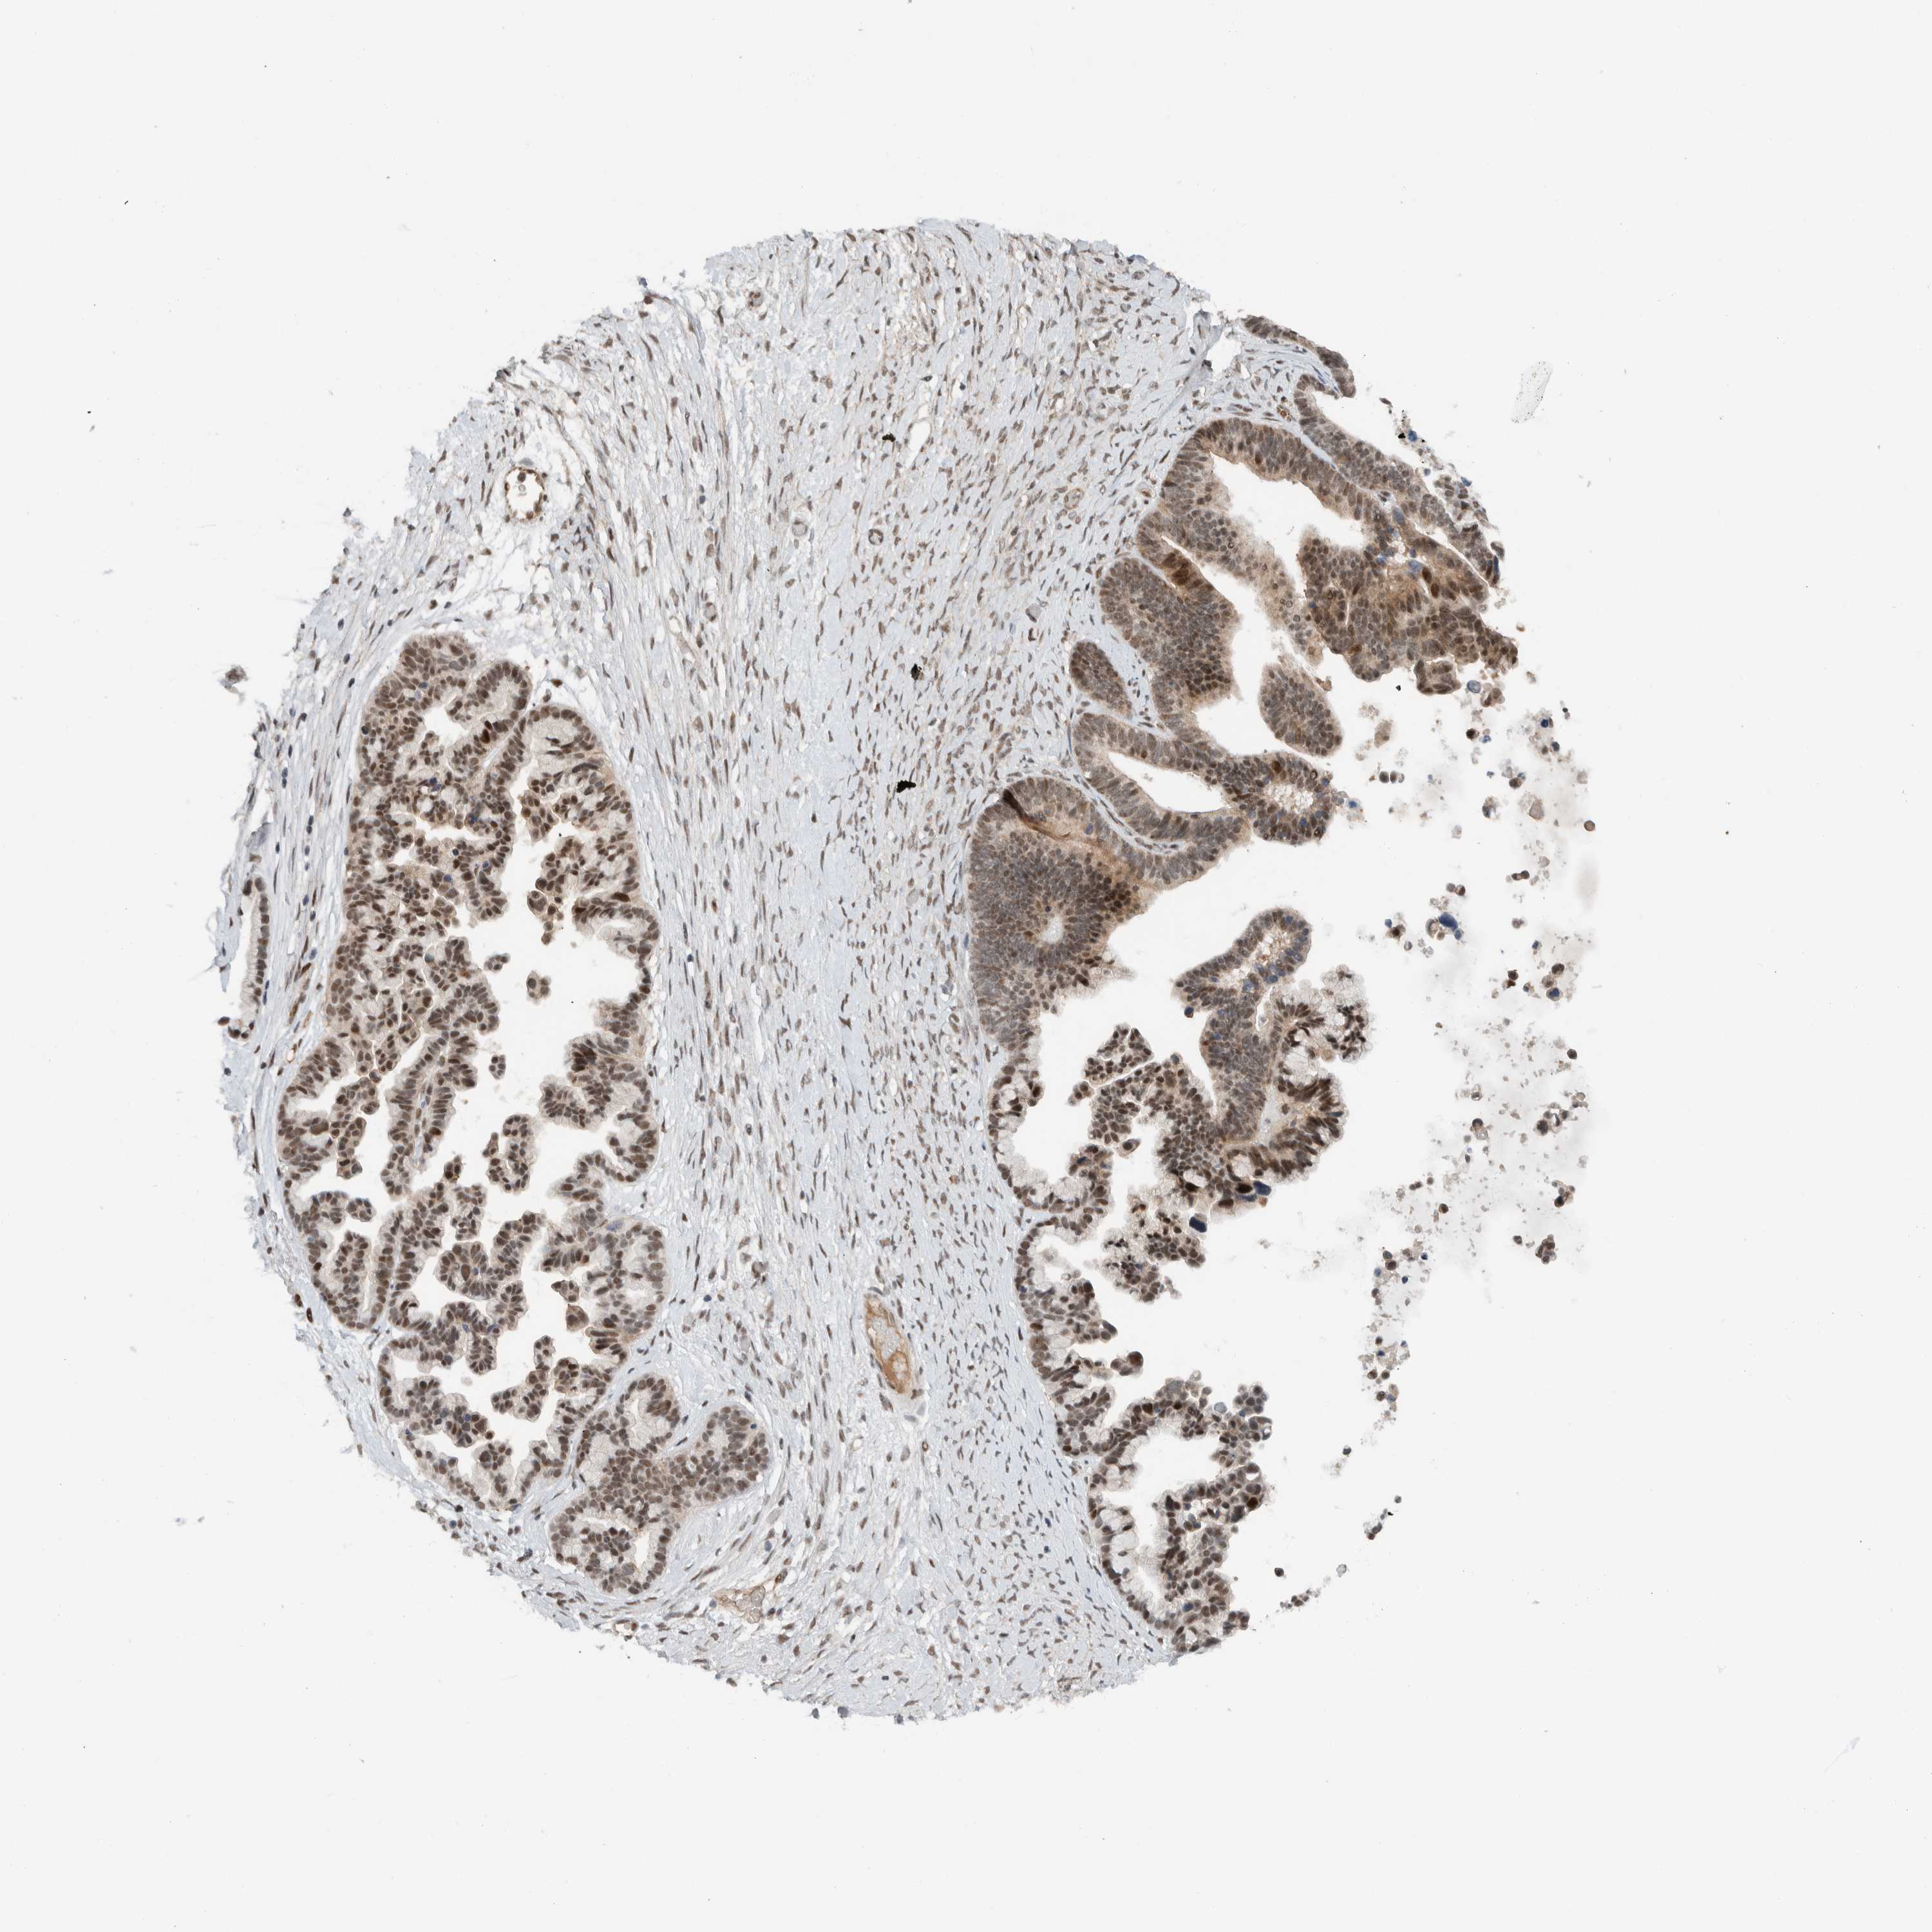

OVARIAN CANCER - Protein expressioni

A mouse-over function shows sample information and annotation data. Click on an image to view it in a full screen mode. Samples can be filtered based on level of antibody staining by selecting one or several of the following categories: high, medium, low and not detected. The assay and annotation is described here.

Note that samples used for immunohistochemistry by the Human Protein Atlas do not correspond to samples in the TCGA dataset.

Antibody stainingi

Antibody staining in the annotated cell types in the current human tissue is reported as not detected, low, medium, or high, based on conventional immunohistochemistry profiling in selected tissues. This score is based on the combination of the staining intensity and fraction of stained cells.

Each image is clickable and will lead to virtual microscopy that enables deeper exploration of all samples and also displays staining intensity scores, fraction scores and subcellular localization as well as patient and tissue information for each sample.

Antibody HPA065325

Cystadenocarcinoma, serous, NOS